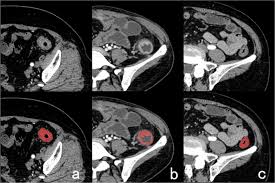

Can ct scan detect colon cancer? Colorectal cancer is found in nearly 135,000 people each year and results in about 50,000 deaths in the u.s. What happens before the cat scan? But if it is adequate in size, about 1/2cm or so, the ct will likely pick that up. Ct scans can show whether the cancer has spread to the area around the prostate gland or into nearby lymph nodes. A ct scan may see irregularities in the liver that may be malignant. Colon cancer develops when tumorous growths develop in the large intestine. Ct scans help doctors diagnose and treat medical conditions such as pancreatic cancer. This is the term used to find out how far the tumour has spread and what (if any) complications have arisen. It occurs both in men and in women. Cancer of the pancreas is rarely diagnosed until it is in the final stages, which is why yes, it can. Metastatic colon cancer can be treated with chemotherapy, which is known to be the standard treatment for metastatic colon cancer, apart from chemotherapy, treatments like radiation therapy and targeted therapy can also be. Find out about symptoms and risk factors for colon cancer, also called colorectal cancer.

Colon Cancer Ct Scan Stock Image C047 9257 Science Photo Library from media.sciencephoto.com This screening test allows your doctor to carefully examine your colon for signs of polyps (abnormal growths on the inside surface of the colon that below, you can learn about the different types of screening tests for colorectal cancer. What are hereditary colon cancer syndromes? Knowing this helps you and your doctor choose the best treatment options. Ct scanners first began to be installed in 1974. It usually begins as small, noncancerous (benign) clumps of cells called. Feline cancer initially manifests as a lump or bump on any parts of the body. Ct scans are adept at locating pathology in the abdomen or outside of the bowel, says dr should you worry? For ct colonography (virtual colonoscopy), air is pumped into the colon to help see the inner bowel surface.

Imaging Of Colorectal Cancer The Clue To Individualized Treatment from www.degruyter.com Staging tests may include imaging procedures such as abdominal, pelvic and chest ct scans. Ct scan result colon cancer staging. Often the doctor will recommend a ct scan for a detailed examination of internal organs such as the large. A ct scan can often detect evidence of a growth or tumor. Colon cancer refers to cancer diseases that occur in the large and small intestine. If my own mother asked me what she should do to prevent colon cancer, i would tell her to this test is essentially a cat scan of the colon, designed to find large polyps and cancers. Find out about symptoms and risk factors for colon cancer, also called colorectal cancer. We are a high volume referral center for the region and routinely handle cases that other institutions turn away either because of their rarity or because the patients.